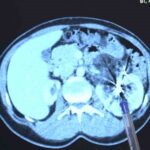

Zorlu bir ameliyatı başarıyla tamamlayan Bursa Medicana Hastanesi Üroloji Uzmanı Doç. Dr. Ahmet Şahan, hastanın durumunun şuan iyi olduğunu belirterek, “Nurcan Hanım 35 yaşında bize İzmir’den geldi. Doğuştan tek böbrekli bir böbreği küçük olduğu için işlevsiz durumda. Sağlam böbreğinde ise 2016’da tanısı konmuş giderek büyüyen iyi huylu “anjiomyolipomu” denilen 12 santimetre boyutunda bir kitlesi var. Bu kitle artık böbreğin damarlarını içerisine almış komplike bir kitle durumunda. Hastaya iki kez anjioembolizasyon tedavisi uygulanmış fakat başarısız olduğu için kitle büyümeye devam etmiş. Kadınlarda 4 santimetreden büyük anjiomyolipomular kendiliğinden kanayarak yaşamı tehlike altına attığı için bu kitlelerin alınması gerekiyor. Tek böbrekli olunan durumlarda böbreğin tamamen alınması durumu da söz konusu olabiliyor. Bu riske girmemek için çoğu merkez de embolizasyona başvurmuş. Hasta bize geldiğinde bu işi yapabileceğimizi söyledik. 2 saat süren kapalı bir ameliyatla kitleyi tamamen çıkardık ve hastamızı 3 gün içerisinde taburcu ettik. Hastamızın değerli şuan iyi durumda. Hastamızı diyalizden kurtarıp kapalı bir ameliyatla sağlığına kavuşturabildiğimiz için çok mutluyuz” dedi.